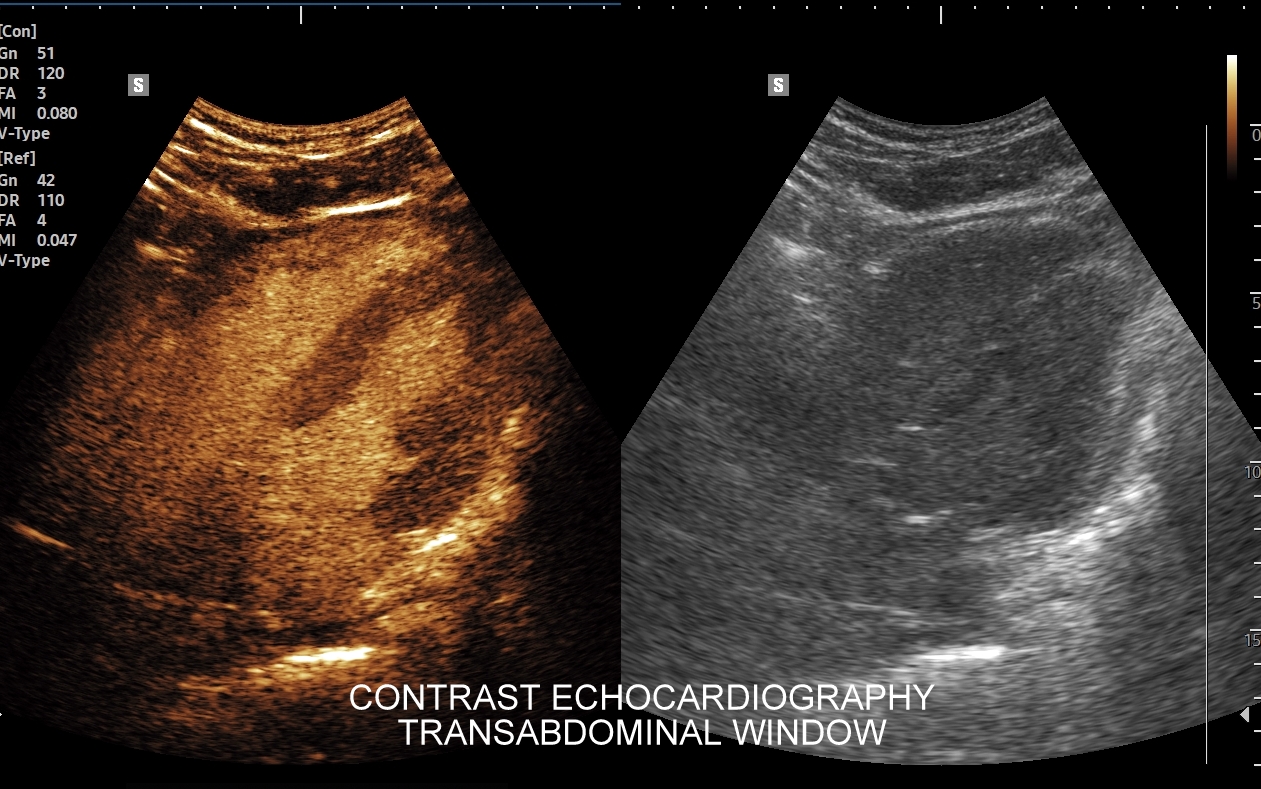

Badanie echokardiograficzne, nazywane także echo serca lub USG serca jest jedną z podstawowych metod diagnostyki kardiologicznej. W badaniu tym ocenia się zarówno morfologię narządu, jak i jego funkcję w postaci pomiarów wielkości jam serca, grubości mięśnia sercowego, czynności skurczowej oraz rozkurczowej lewej i prawej komory, oceny funkcji zastawek serca, wyglądu wsierdzia, osierdzia, a także w postaci pomiarów aorty, poszukiwania obecności patologicznych objawów sercowych związanych z chorobami innych narządów (np. choroby płuc, nadciśnienie tętnicze).

Specjalista chorób wewnętrznych z wieloletnią praktyką kardiologiczną i naczyniową. Szkolenie USG serca odbywał w Pododdziale Kardiodiagnostyki w Klinice Chirurgii Serca Akademii Medycznej we Wrocławiu. Jeden z najbardziej doświadczonych sonografistów w Polsce. Posiada ponad 25-letni staż kliniczny i szkoleniowy w Polsce oraz zagranicą (Wielka Brytania, Niemcy, Austria, Włochy). Wykonał ponad 40.000 badań USG. Wprowadził do rutynowego zastosowania w Polsce takie procedury diagnostyczne jak USG z kontrastem (CEUS) oraz multiparametryczne badania USG (MPUS). Certyfikowany lekarz Polskiego Towarzystwa Ultrasonograficznego z zakresu badań naczyniowych. Na co dzień dr Szczepański zajmuje się przeglądami zdrowia oraz specjalistyczną diagnostyką z zakresu chorób wewnętrznych i serca.